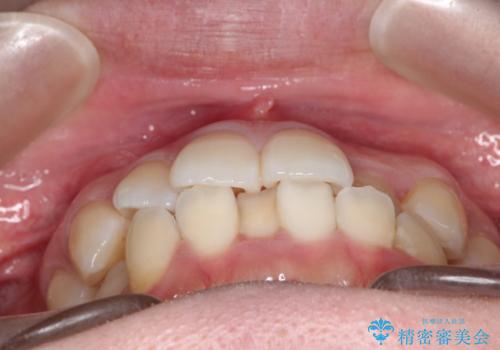

- 主訴:口元を下げて前突感を無くしたい、下の歯の凹凸も無くしたい

右側第二小臼歯、左側第一小臼歯、下顎両側第一小臼歯を抜歯しワイヤ-矯正を行いました。

骨格的顎の変位を認めたため、顔貌に対しピッタリ上下の歯の正中を合わせることは難しいと説明し、上下左右計4本小臼歯を抜歯しワイヤー矯正治療を行いました。